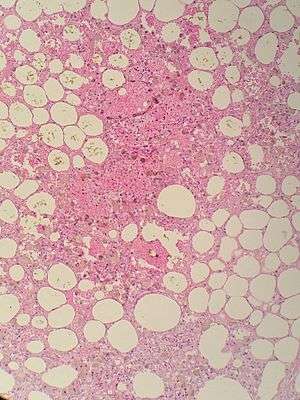

| Sclerosing mesenteritis , note the hemosidirin, chronic inflammation | |

The disorder is identified by histopathology showing fat necrosis, fibrosis and chronic inflammation of the small intestine. Examination of the mesentery may indicate a solitary mass, but diffuse mesentery thickening is common.[2][4]